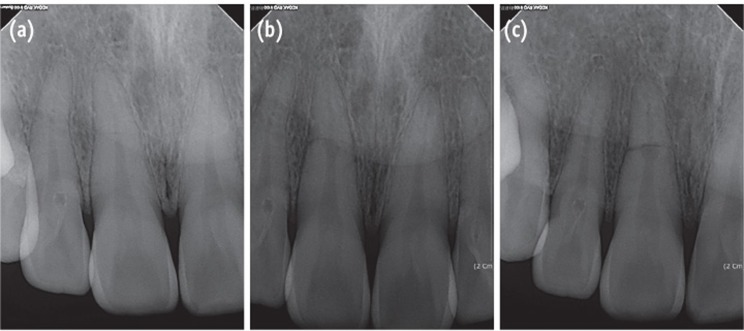

A 33-year-old man presented to the Department of Conservative Dentistry at the Wonkwang University Dental Hospital (Iksan, Korea) with a complaint of discomfort of the maxillary right central incisor during mastication. Two days before, the tooth had impacted against a rigid object. The patient's medical history was noncontributory. Radiographic examination showed a horizontal fracture in the middle third of the root of the tooth and a slight displacement of the apex (Figure 1a). Intraoral examination revealed that all maxillary teeth had normal responses to pulp vitality tests, no mobility, and no discolored crown. Since the maxillary central incisor showed no signs of mobility or pathology, the patient was followed up without any splint appliances. His occlusion was checked and adjusted to eliminate loading on the traumatized tooth during function.

Four weeks after the trauma, a radiolucent area appeared intra-canally on the apical portion of the coronal fragment and it continued to progress until 6 weeks of observation (Figures 1b and 1c). Root canal treatment was initiated on the coronal fragment with K-file and irrigated with 5% sodium hypochlorite. Working length was established with an apex locator (DentaPort ZX, Morita, Kyoto, Japan). Special care was taken to instrument within the coronal fragment. After 2 months of intracanal calcium hydroxide dressing, the canal was obturated with mineral trioxide aggregate (MTA, ProRoot, Dentsply, Tulsa, OK, USA) (Figure 2a).

At the 2-year follow-up evaluation, the patient did not report any clinical symptoms. Complete healing of the root fracture with the interposition of hard tissue between the fragments was observed on the periapical radiographs (Figure 2c).

In Case 1, internal resorption around the coronal fracture line was observed at approximately 4 weeks after the trauma. Andreasen et al. reported 3 types of resorption in patients with root fractures, (1) external surface resorption (ESR), (2) internal surface resorption (ISR), and (3) internal tunneling resorption (ITR).1 Andreasen stated that these root resorption processes are usually correlated with healing processes and therefore require no interceptive treatment. The pathogenesis of internal root resorption and subsequent healing following root fracture result from an interplay between the exposed dentin, a damaged but uninfected pulp, and the in-growth of vital tissue.1,7 In Case 1, the ISR type of root resorption was apparent on radiographic examination at approximately 4 weeks, and therefore a process of healing was expected. Root canal treatment was unfortunately initiated without a full knowledge of the healing process of root fractures. At the 2-year follow-up examination, the tooth showed complete healing on the radiograph. However, the tooth supposedly could have healed spontaneously, even without root canal treatment. For the successful management of root fractures, it is important to understand the healing patterns thoroughly.

Andreasen and Hjorting-Hansen classified the healing of root-fractured teeth into four groups, (1) healing with hard tissue, (2) healing with the interposition of hard and soft tissue, (3) healing with interposition of soft tissue, and (4) no healing.12 The factors influencing the healing of a root-fractured tooth include the patient's age, stage of root growth, mobility of the coronal fragment, and diastasis of the fragments.1 In the present patients, injury factors (e.g., fragment diastasis and mobility of the coronal fragment) exerted a strong influence on healing at the fracture line and on pulpal necrosis. Case 1 had small diastasis of less than 0.5 mm and no mobility, and the tooth healed with hard tissue and with the evidence of a spontaneous healing process such as ISR. Case 2 showed extrusive luxation of the crown fragment with a large amount of diastases. It was impossible to determine whether the pulp was vital because root canal treatment had been already initiated by the emergency dentist. The follow-up radiographs showed healing with hard and soft tissue. Case 3 showed lateral luxation of the crown fragment with a large amount of diastases. Interposition of soft tissue with pulp necrosis of coronal fragment was also observed. Increasing diastases between fragments reportedly increases the risk of pulp necrosis, and decreases the likelihood of hard tissue healing.13 According to a report, the frequency of pulp necrosis is stable with diastasis of up to 1 mm, whereas hard tissue healing shows stable values up to 0.5 mm.13

Figure 1

(a) The radiograph of the initial visit shows a horizontal root fracture line on the maxillary right central incisor; (b) The 4-week follow-up radiograph shows internal resorption around the fracture line; (c) The 6-week follow-up radiograph shows that the internal resorption site is larger and more distinct.

Figure 2

Radiograph of the tooth. (a) After root canal treatment; (b) At the 1-year follow-up evaluation; (c) At the 2-year follow-up evaluation. 2-year follow-up radiograph reveals healing with the interposition of hard tissue between the fragments.